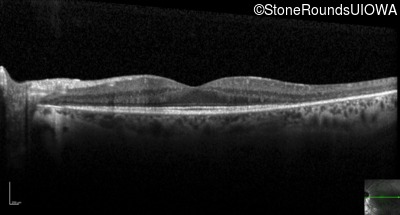

Optical Coherence Tomography - Left - 20/20

Exemplar / OCT Stack

OCT Stack